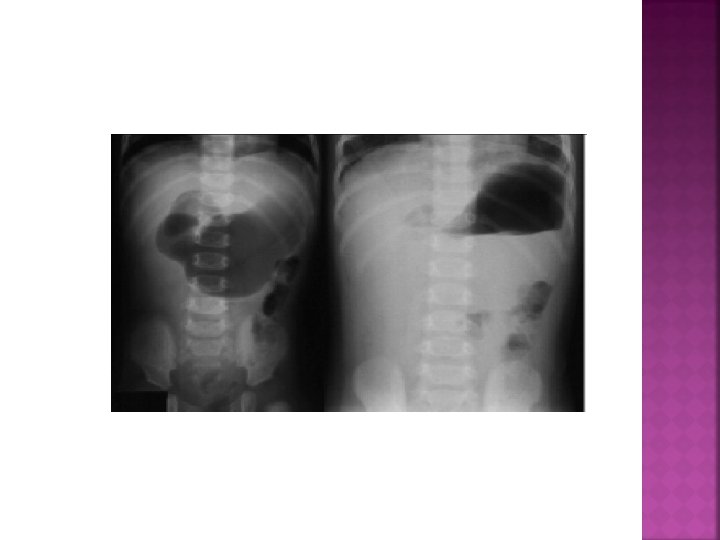

LABORATUVAR Direkt grafi (Fekalit, sağ alt kadranda hava sıvı seviyesi, Psoas gölgesi silinebilir, skolyoz)

AKUT APANDİSİT